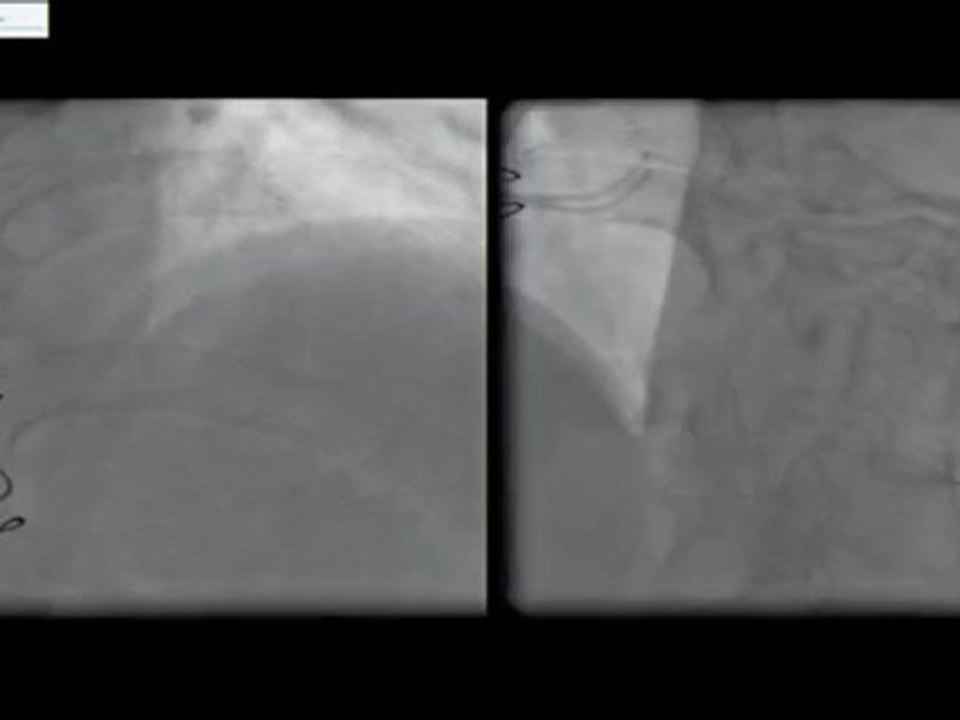

12 below knee by-pass graft instent restenosis and posterior tibial artery angioplasty incathlab.com